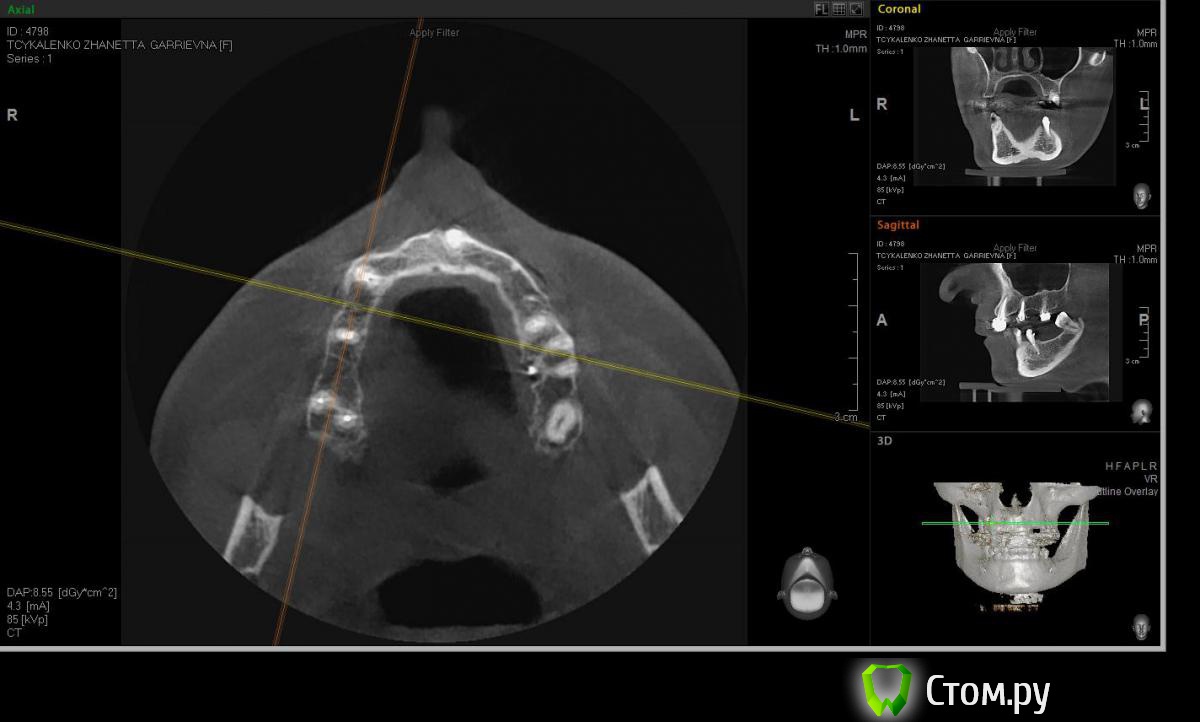

Евгений Ходыкин Опубликовано 20 мая, 2014 Поделиться Опубликовано 20 мая, 2014 Коллеги, прошу помощи в определении варианта аугментации в области 1.4 для адекватной в протетическом плане постановки имплантата. Адекватно ли здесь будет расщепление гребня при той оси импланта, которую я схематично выставил? Всем заранее спасибо) Ссылка на комментарий

АнтонТЛТ Опубликовано 20 мая, 2014 Поделиться Опубликовано 20 мая, 2014 Тонкий имплантат и НКР. Угол позиционирования имплантата делал бы другой. 4 Ссылка на комментарий

Евгений Ходыкин Опубликовано 20 мая, 2014 Автор Поделиться Опубликовано 20 мая, 2014 Если сделать по гребню, ангуляция на абатменте более 15 выходит, рассматривал этот вариант) Ссылка на комментарий

Евгений Ходыкин Опубликовано 20 мая, 2014 Автор Поделиться Опубликовано 20 мая, 2014 а что мешает сделать на 15 градусном абатменте?.. и ради этого идти на намного более объёмную хирургию?Сорри, если заблуждаюсь конечно, но более 15 уже не есть гуд касательно аксиальной нагрузки на имплант. А если все-таки ставить его "правильно", что подскажете?) Ссылка на комментарий

Евгений Ходыкин Опубликовано 20 мая, 2014 Автор Поделиться Опубликовано 20 мая, 2014 Суть в том, что изначально не правильно угол замерилиДак изначально я замерил строго по гребню, в условиях наибольшей ширины гребня, там угол под 30 и выходил. При ангуляции как у 1.5 у меня и получается дефицит кости, что примерно изобразил на схеме постановки имплантата. Поправьте, если не прав... Ссылка на комментарий